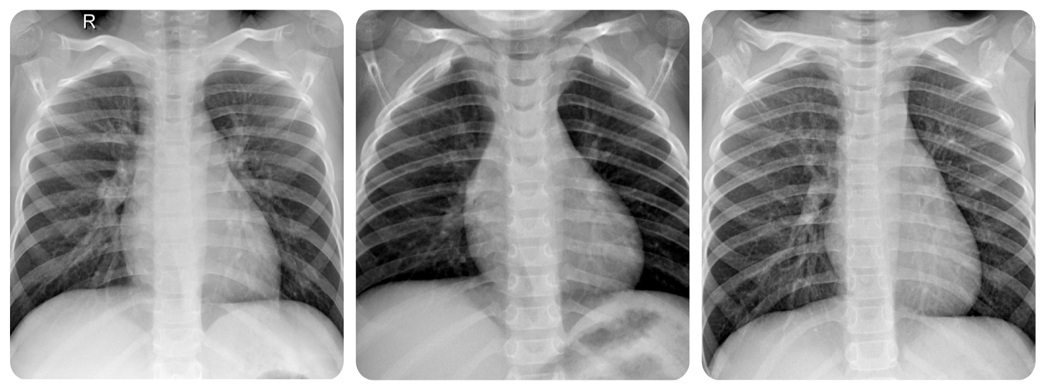

본 연구에서는 학습 데이터 5,216장(정상 1,341장, 폐렴 3,875장), 테스트 데이터 624장(정상 234장, 폐렴 390장)으로 구성된 ChestXRay2017 Dataset[9]을 사용하였다. 해당 Dataset은 주로 1~5세 소아 환자의 흉부 X-ray 영상으로 구성되어 있다. 그림 7은 정상 환자의 흉부 X-ray 예시 이미지를, 그림 8은 폐렴 환자의 흉부 X-ray 예시 이미지를 나타낸다.

Fig. 8.

Chest X-ray images of children with pneumonia

소아 X-ray 영상은 성인과 비교할 때 뚜렷한 해부학적‧영상학적 차이를 보인다. 예컨대, 소아는 해부학적으로 흉곽 크기가 작고, 연조직 발달이 미흡하며, 뼈조직의 석회화가 완전히 이루어지지 않아 X-ray의 투과도가 성인에 비해 높다. 그 결과, 폐 실질의 혼탁과 폐렴 병변에 의한 음영 증강 등 구조 변화가 영상 상에서 더욱 명확하게 드러나게 된다. 이러한 점은 폐렴 병변의 위치와 확산 형태를 비교적 선명하게 관찰할 수 있게 하며, 이는 인공지능 모델이 소아 영상에 대해 상대적으로 높은 진단 민감도와 특이도를 달성할 수 있는 잠재적 이점을 제공한다.

임상적으로도 소아와 성인 폐렴은 영상 소견에서 차이를 보인다. 소아 폐렴은 주로 폐포성 병변이 많고, 폐 실질의 뚜렷한 음영 증가 및 침윤이 영상에서 직접적으로 나타난다. 이에 반해, 성인 폐렴은 간질성 침윤 패턴, 기저 폐질환(만성 폐쇄성 폐질환, 폐 섬유화 등) 동반, 노화에 의한 해부학적 변화 등이 복합적으로 작용하여 영상의 비특이성과 구조적 복잡성이 커지는 경향이 있다. 이러한 성인의 해부·병리학적 요인은 실제 진단 과정에서 영상 판독 일관성과 정확도를 저하시킬 수 있다.

또한, 성인은 만성 폐쇄성 폐질환(COPD), 심부전, 폐 섬유화 등 다양한 만성 질환의 기저 질환을 보유할 수 있으므로, 폐렴 병변이 다른 구조물과 중복되거나 명확한 경계 없이 복합적으로 나타나는 경우가 많다. 반대로, 소아 환자는 기저 질환이 거의 없고, 영상 상에 단독 병변이 드러나는 경우가 상대적으로 많아 딥러닝 기반 진단 모델의 성능 산출에 유리한 환경을 제공한다.